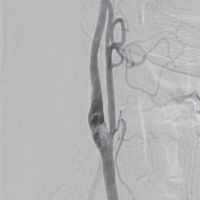

Karotis-Rekonstruktion

Im Leistungsbereich Karotis-Rekonstruktion werden Patienten betrachtet, bei denen eine chirurgische Entfernung arteriosklerotischer Plaques aus der Arteria carotis interna (Karotis-Thrombendarterektomie bzw. Karotis-TEA) durchgeführt wurde.